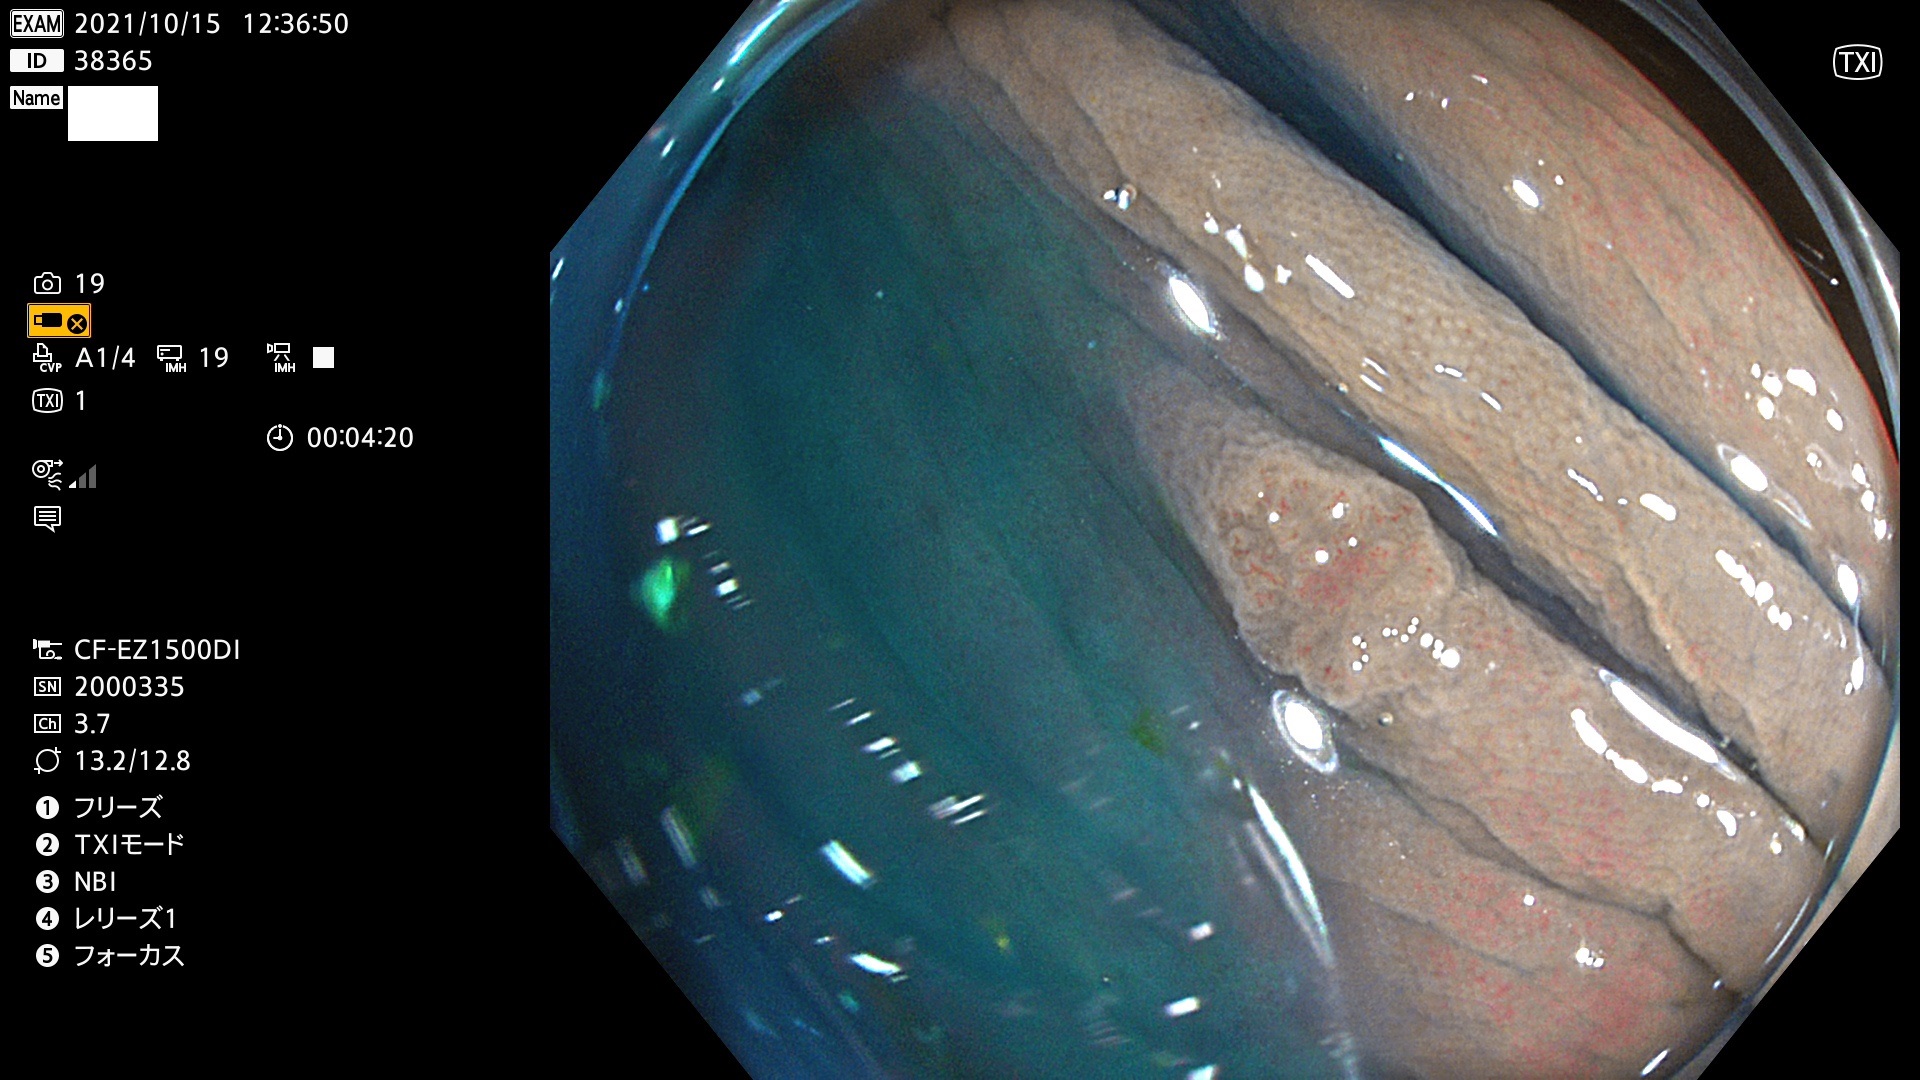

38300 38301 38302 38303 38304 38306 38307 38308 38309 38310 38311 38312 38313 38314 38315 38316 38317 38319 38321 38322 38323 38324 38325 38327 38331 38332 38333 38334 38337 38338 38339 38340 38341 38343 38346 38348 38349 38350 38351 38352 38353 38354 38355 38358 38359 38360 38361 38362 38363 38365 38366(SSAP) 38368 38369 38370 38371(SSAP) 38372 38374 38375 38376 38377 38378 38380 38381 38382 38383 38384 38385 38386 38388 38389 38391(SSAP) 38395 38397 38399

発見困難で危険性の高い平坦型病変(上記100名より抽出)